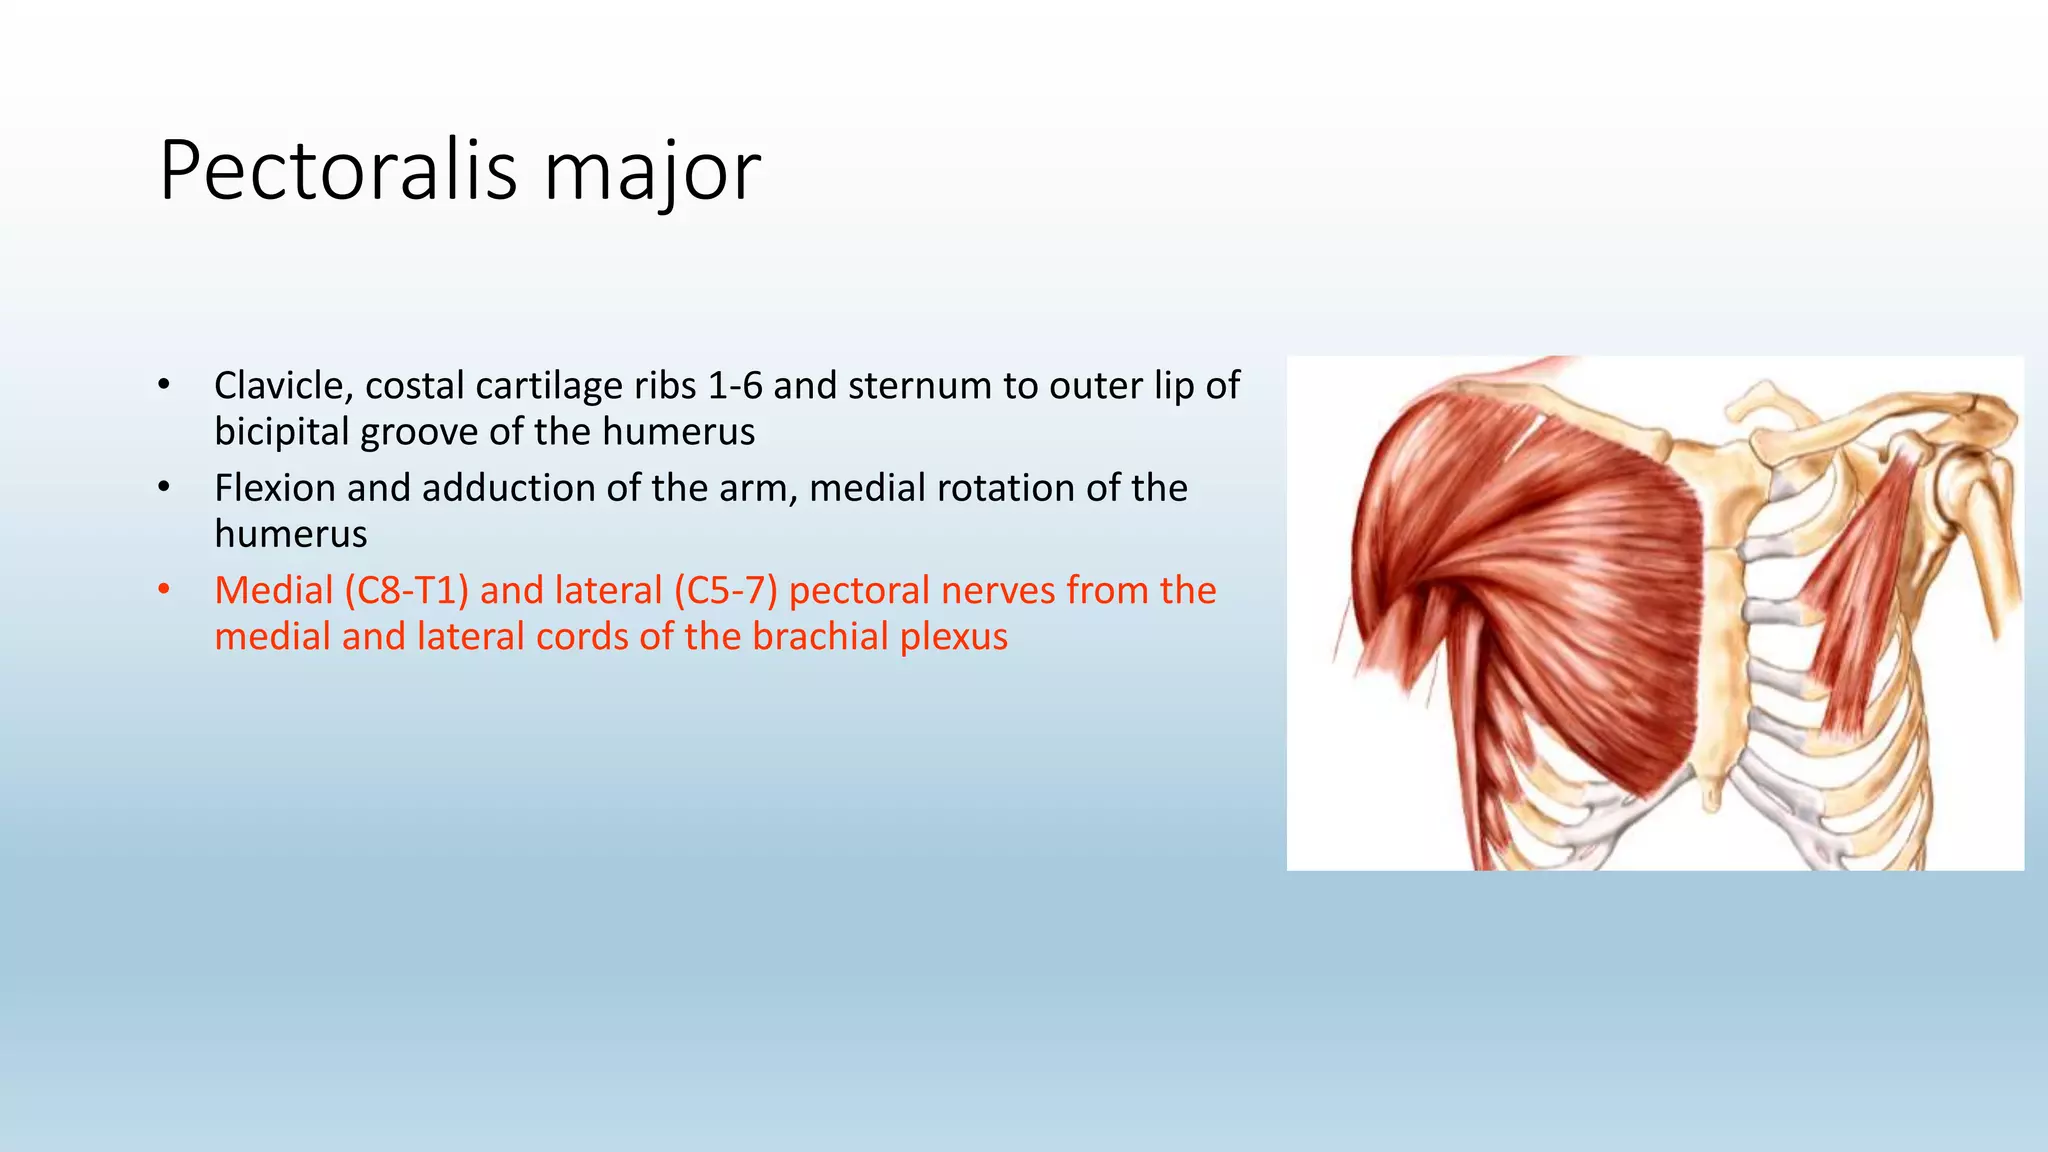

The document summarizes an anatomy revision session on the upper limb. It discusses various muscles of the upper limb including their origins, insertions, innervations and functions. Key muscles covered include the pectoralis major and minor, serratus anterior, deltoid, biceps brachii, brachialis, coracobrachialis, and triceps. It also discusses the rotator cuff muscles and muscles of the forearm including flexor carpi ulnaris and radialis. The session aims to help students identify upper limb muscles and understand their relations to nerves.